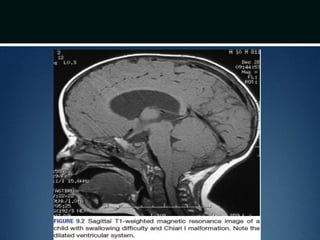

Clinical presentation..

โ€ข Pertaining to brainstem, cerebellar and spinal cord dysfunction

โ€ข Usualy present in infancy/early childhood

โ€ข Worst outcome if symptoms appear before 3 months age

โ€ข Stridor, apnea and dysphagia resulting in aspiration ๏ƒ  might cause

death

โ€ข Nystagmus โ€“ earliest sign of cerebellar dysfunction

โ€ข Initial spinal cord symptoms (weakness, bowel and bladder

dysfunction) โ€“ secondary to inadequate formation of the lower spinal

cord

Diagnosis

โ€ข MRI โ€“ cranial and spinal

โ€ข Plain dynamic cervical spine radiographs

๏ƒ  instability

Clinical presentation.. โ€ข Pertainingto brainstem, cerebellar and spinal cord dysfunction โ€ข Usualy present in infancy/early childhood โ€ข Worst outcome if symptoms appear before 3 months age โ€ข Stridor, apnea and dysphagia resulting in aspiration ๏ƒ  might cause death โ€ข Nystagmus โ€“ earliest sign of cerebellar dysfunction โ€ข Initial spinal cord symptoms (weakness, bowel and bladder dysfunction) โ€“ secondary to inadequate formation of the lower spinal cord

Diagnosis โ€ข MRI โ€“cranial and spinal โ€ข Plain dynamic cervical spine radiographs ๏ƒ  instability